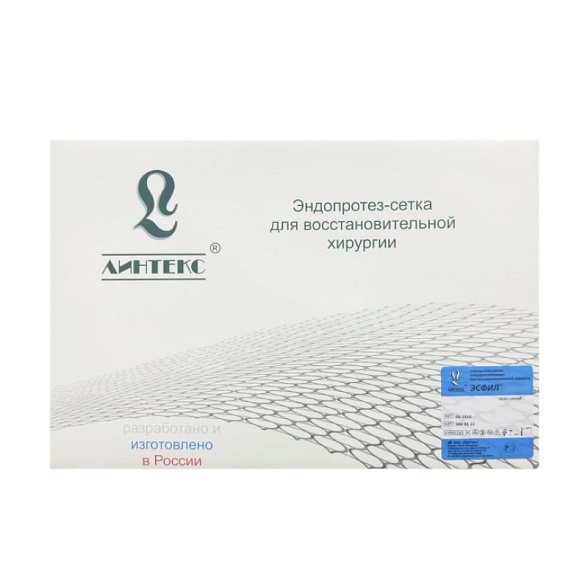

Эндопротез-сетка (сетка хирургическая) полипропиленовый для восстановительной хирургии ЭСФИЛ стандартный, 30х30 см, Линтекс

Эндопротез-сетка полипропиленовая ЭСФИЛ стандартная 30х30 см (Линтекс)

| Бренд / Производитель | Линтекс (Lintex), Россия |

| Стерилизация | Изделие поставляется стерильным (обычно методом ЭОГ — окисью этилена или радиационным) |

| Упаковка | Индивидуальная двойная: внутренний стерильный чехол и внешняя защитная упаковка. |